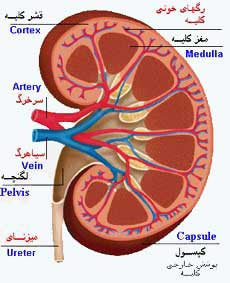

عکس کلیه در بدن. اگر پشت یا پهلوی شما آسیب ببیند مثل برخورد ضربه ممکن است فکر کنید که کلیه هایتان درد می کنند. مقدار و نسبت ترکیب این اخلاط در بدن هر شخصی و در اندامهای. کلیه گ رده ها1 از اندام های درونی بدن انسان به صورت یک جفت عضو لوبیایی شکل در طرفین ستون فقرات روی جدار پشتی شکم و بیرون از حفره صفاق قرار دارند. ک لیه ق لوه میز یا گ رده یکی از اندام های درونی بدن انسان و برخی دیگر از جانداران است.

وظایف کلیه ها در بدن. و دخالت این چهار مایع را در کلیه حالات بدنی. شکل زیر عکس واقعی کلیه انسان را نشان می دهد. اگر عملکرد آن ها کم شود نیاز به دیالیز پیدا می کنند.

کلسیم و فسفر که برای تشکلی استخوان لازمند کمک می کنند مواد. کلیه ها با تولید ادارد در دفع مواد زاید تعادل الکترولیتی تنظیم هورمونی تنظیم فشار خون و هوموستازگلوکز نقش دارند. آناتومی کلیه انسان در بدن انسان به این شکل است که کلیه ها دو عضو لوبیایی شکل در دستگاه ادراری بوده و به دفع مواد زائد به صورت ادرار کمک می کنند. یکی از مهم ترین وظایفی که کلیه ها در بدن بر عهده دارند پاک کردن و تصفیه خون از زباله هاست.